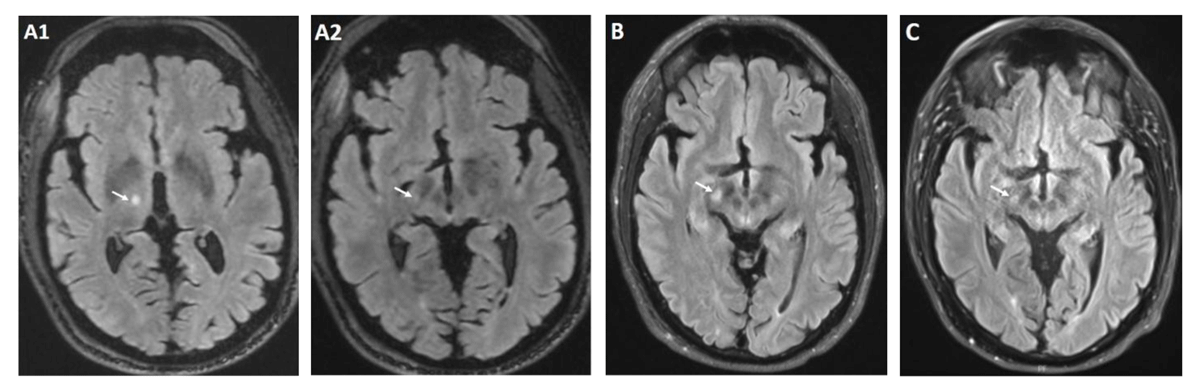

Figure 1

Brain MRI T2 FLAIR post procedure.

Immediately post procedure lesion at Vim (A1) with very slight extension to STN (A2) 1 month after procedure and onset of chorea with increased signal intensity involving the right STN (B) 8 months after procedure with near resolution of STN signal hyperintensity (C).